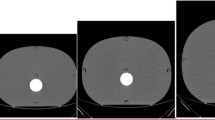

Low-contrast visibility

The low-contrast visibility is best for the MDCT. The 0.5% contrast objects were less visible in the UHRCT NR mode images than in the MDCT ones. For the UHRCT SHR and HR modes compared with MDCT, the edges of the low-contrast object were more sharply delineated (Fig. 4). In Tables 4 and 5, the number of visible contrast objects is given. The extra dose necessary for the UHRCT NR mode to have same low-contrast object visibility was 14%. For the HR and SHR modes, this dose increase was approximately 23%.

Images of the Catphan low-contrast objects in the CTP515 module acquired in NR, HR and SHR modes of the UHRCT and on the MDCT (left) at a CTDIvol of 9.1 mGy and (right) for the same low-contrast detectability, the CTDIvol is noted. Note that the window width is not the same for all images; for the SHR and HR modes, it is 60 (left) and 50 (right) and for the NR and MDCT it is 30